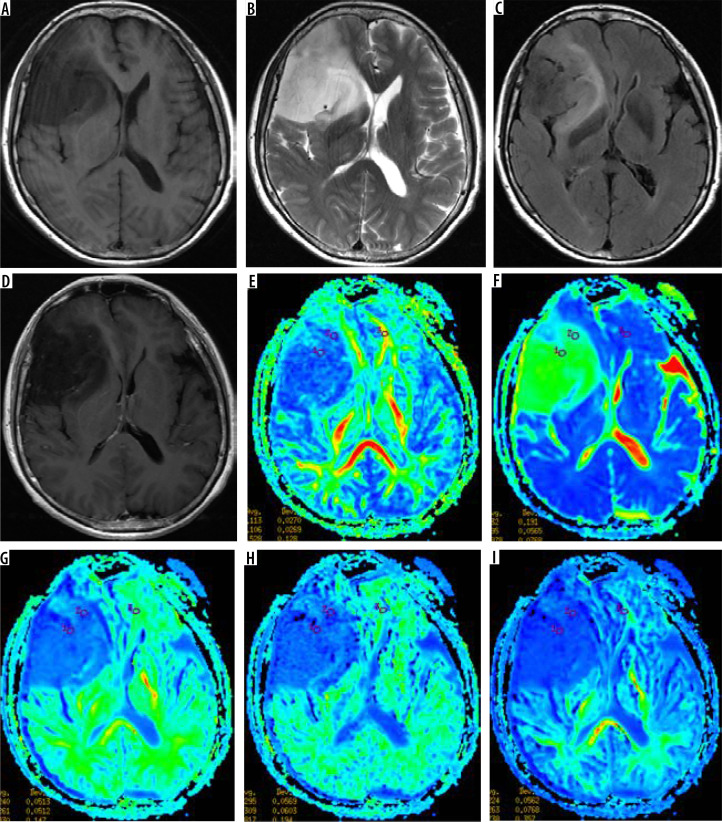

Material and methods: Twenty-five patients with WHO grade II gliomas were retrospectively included. Patients underwent routine MRI and DKI scanning before surgery, measuring tumoural solid portion, peritumoral oedema, and normal-appearing white matter (NAWM) DKI parameters, including fractional anisotropy (FA), mean diffusivity (MD), mean kurtosis (MK), axial kurtosis (Ka), and axial radial kurtosis (Kr). The DKI parameter corrections were made (tumour or oedema parameters values divided by the NAWM value) to obtain the rFA (ratio of FA), rMD (ratio of MD), rMK (ratio of MK), rKA (ratio of KA), and rKr (ratio of Kr) values. Postoperative specimens were made of wax blocks and analysed by Sanger gene sequencing. DKI parameters between the 2 groups were compared by independent sample t-tests. The ROC curve was used to analyse the diagnostic value of each parameter.

Results: Twenty-five patients were diagnosed with IDH-mutant (16 cases) and IDH-wild type (9 cases). The rFA and rMK values in the parenchymal region of IDH wild-type tumour were higher than those of IDH mutant, while the rMD values were lower than those of IDH mutant, and the difference between them was statistically significant (p < 0.05). The values of DKI parameters of peritumoral oedema in the 2 groups were not statistically significant.

Abstract Image